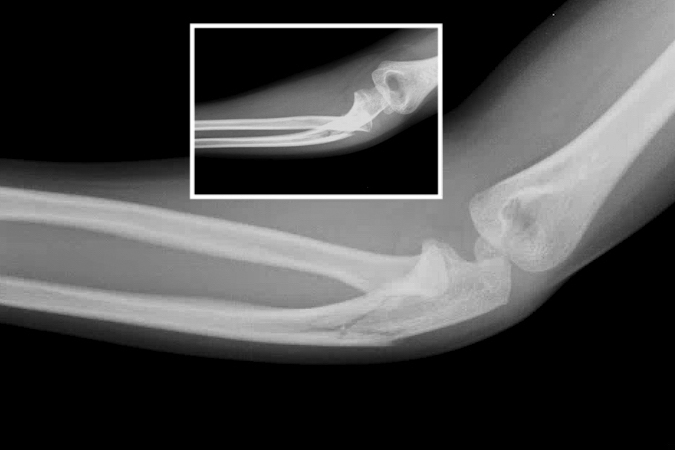

Monteggia fracture

- A Monteggia fracture involves a fracture of the proximal third of the ulna combined with a subluxation or dislocation of the radial head at the proximal radioulnar joint (PRUJ) and the humeroradial joint.1,11,12

- These injuries most commonly occur secondary to a direct blow to the posterior aspect of the ulna, with the elbow extended and the forearm in hyperpronation.16,17

- Monteggia fractures account for <2% of all forearm fractures and are more common in pediatric patients than adults. In children and adolescents, they are usually caused by sports injuries, falls from a height, or motor vehicle accidents.11,13,16

Imaging17

- Radiology studies - X-ray

- AP and lateral orthogonal views with an oblique view are usually adequate.3